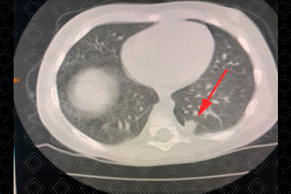

Texto alternativo para a imagem Figura 1. Créditos: Dra. Elazir Mota - Rio de Janeiro/RJ

Descrição da figura 1: Tomografia computadorizada de tórax. Paciente do sexo feminino, com história familiar de câncer pulmonar, apresentando nódulo pulmonar solitário com média de 10 mm, no lobo inferior esquerdo (seta vermelha). Como a paciente pertencia ao grupo de risco (história familiar de câncer de pulmão), foi solicitado controle em 3 meses e/ou PET-CT com biópsia (baseado nos critérios de Fleischner).